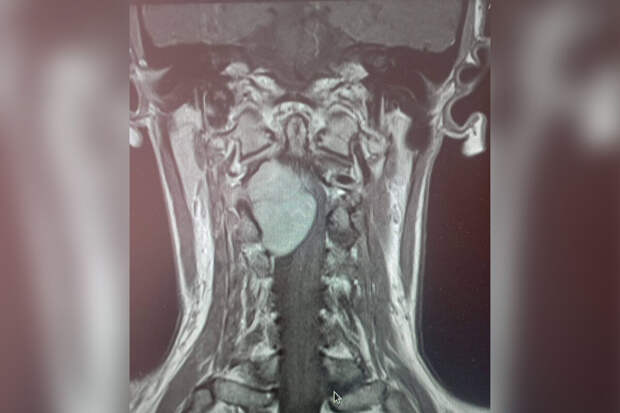

Пациентка обратилась к медикам с жалобами на отнимающиеся руки и ноги. МРТ показало, что проблема кроется в шейном отделе позвоночника, где выросло большое новообразование.

"Шейный отдел - очень опасная локализация. Спинной мозг здесь переходит в головной, кроме того, в шее проходит большая нервно-сосудистая магистраль. Опухоль в этом отделе представляет серьезную угрозу и может привести к парализации", - рассказал нейрохирург больницы Леонид Осолодченко.